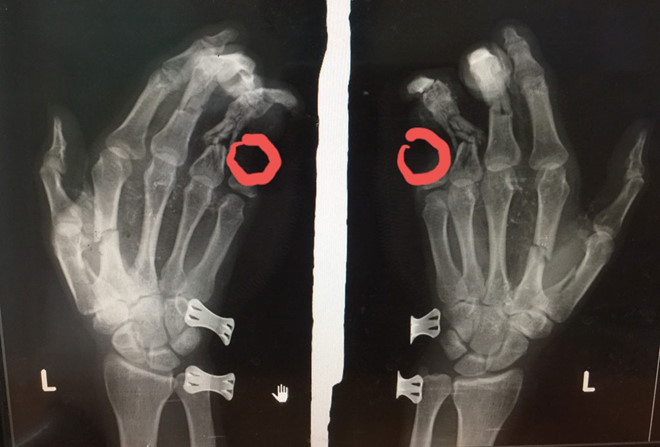

28/05/2020 01:23Điện thoại phát nổ, nam thanh niên bị dập nát bàn tay

Trưa 27/5, Bệnh viện II Lâm Đồng (tại TP.Bảo Lộc, Lâm Đồng) tiếp nhận bệnh nhân Lương Thanh Duy (37 tuổi, ngụ TP.Biên Hòa, Đồng Nai và hiện tạm trú tại P.Lộc Sơn, TP.Bảo Lộc) nhập viện trong tình trạng bàn tay trái và ngón út bị cụt mất 2 đốt do điện thoại phát nổ.

Ngay sau đó, bệnh nhân được sơ cứu, chụp phim và đưa vào phòng mổ phẫu thuật khâu lại vết thương.

Theo lời kể của nạn nhân, vào khoảng 11h45 trưa cùng ngày, anh Duy sử dụng điện thoại vừa cắm sạc pin, vừa chơi game tại nhà trọ (P.Lộc Sơn, TP.Bảo Lộc) thì chiếc điện thoại phát nổ.

Hậu quả, điện thoại phát nổ làm bàn tay trái của anh Duy dập nát, tổn thương nặng và ngón út bị cụt mất 2 đốt. Ngay sau đó, người dân đã đưa anh Duy đến Bệnh viện II Lâm Đồng cấp cứu, điều trị.